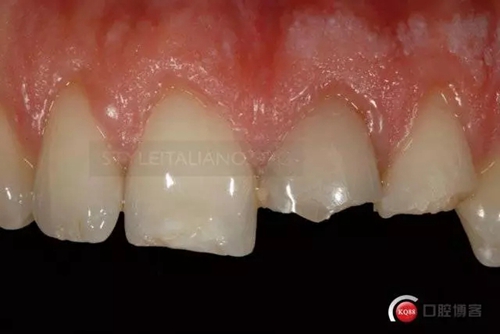

Until the immediate final outcome

Control one month check shows a natural smile

And the vestibular

and palatal tissue healing